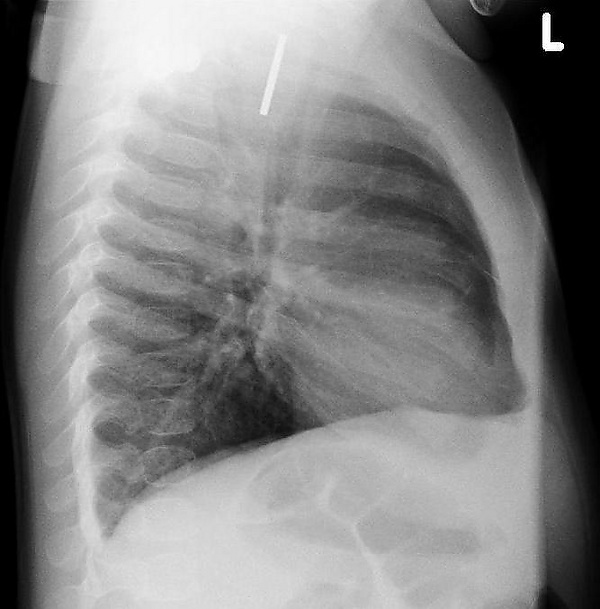

Инородные тела ЖКТ

Одна из распространённых локализаций инородных тел — желудочно-кишечный тракт. Возможные пути проникновения инородных тел — ротовая полость[13] или прямая кишка[14]. Дети чаще проглатывают монеты[15], у взрослых в 75 % случаев инородными телами служили мясные кости[16].

Наиболее часто проглоченные предметы обнаруживают в пищеводе или желудке, реже в глотке или двенадцатиперстной кишке[17].